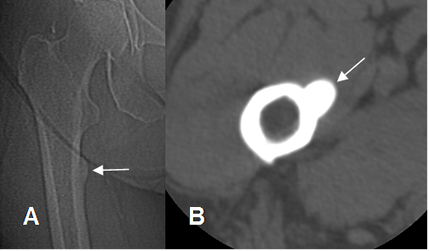

Fig 76. Osteocondroma.

A: Rx AP y B: TAC axial. Area de exostosis en la diáfisis femoral, por osteocondroma.